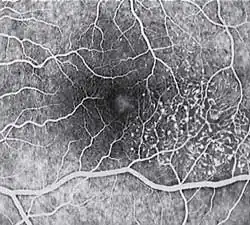

Fluorescein angiography (FA) is helpful in identifying the anomalous vasculature, particularly in the early stages of Type 2 disease. Formerly, FA was essential in making a definitive diagnosis. However, the diagnosis can be established with less invasive imaging techniques such as Ocular Coherence Tomography (OCT) and fundus autofluorescence. Some clinicians argue that FA testing may be unnecessary when a diagnosis is apparent via less invasive means.